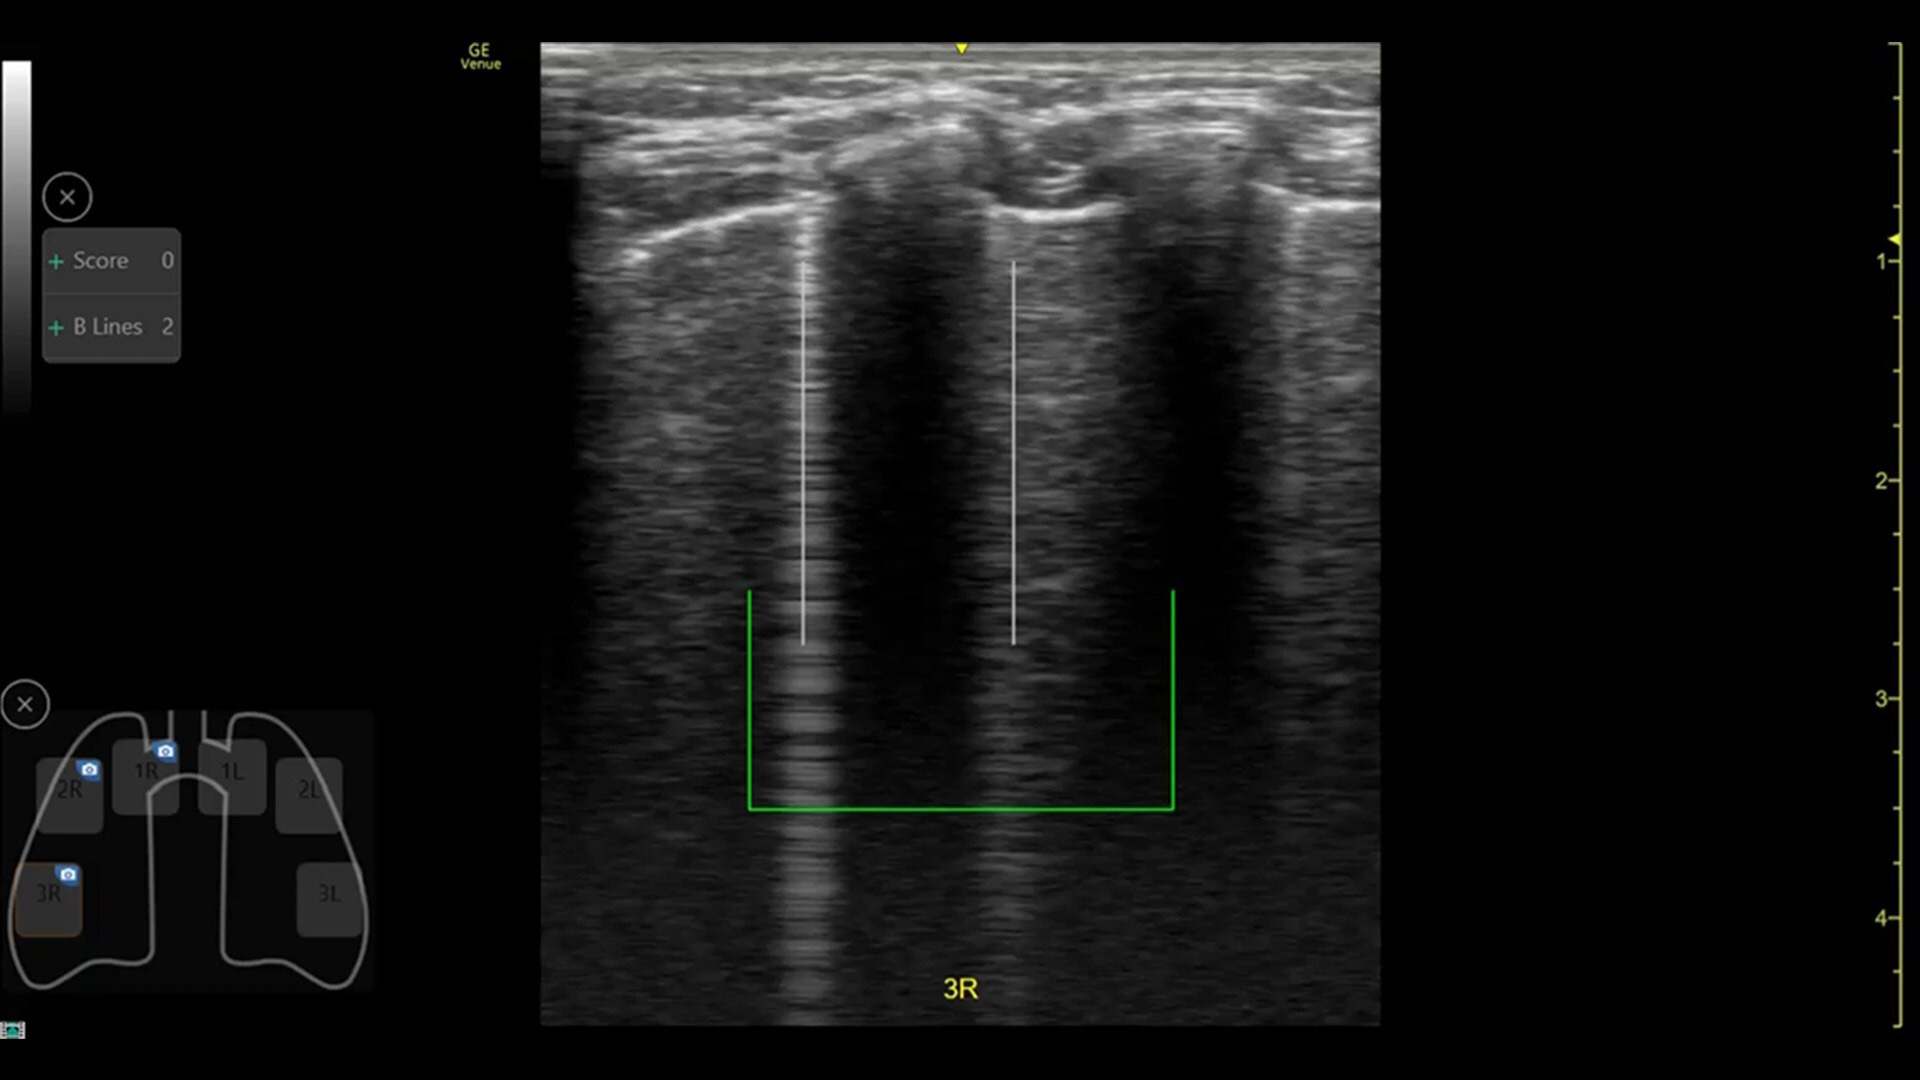

AI-DRIVEN AUTO TOOLS

Advanced and automated clinical tools enabling you to quickly diagnose, treat and determine a care pathway.

Venue Go has been designed and tested to be walk up easy for novice to expert users, and it features a number of AI-enabled automated tools to accelerate clinical workflow while also reducing the fatigue of repeated and difficult tasks. Utilizing proprietary algorithms, we synthesize data from numerous patients to ensure accurate calculations for clinical confidence.